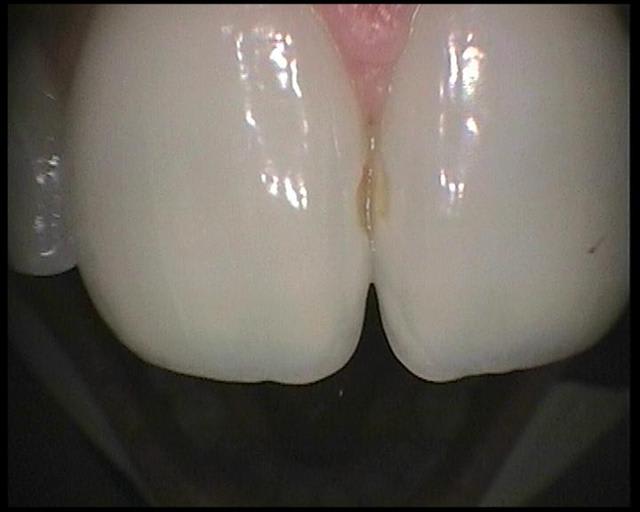

voici les images prises avec la sopro 595

Images en vrac de sopro 595